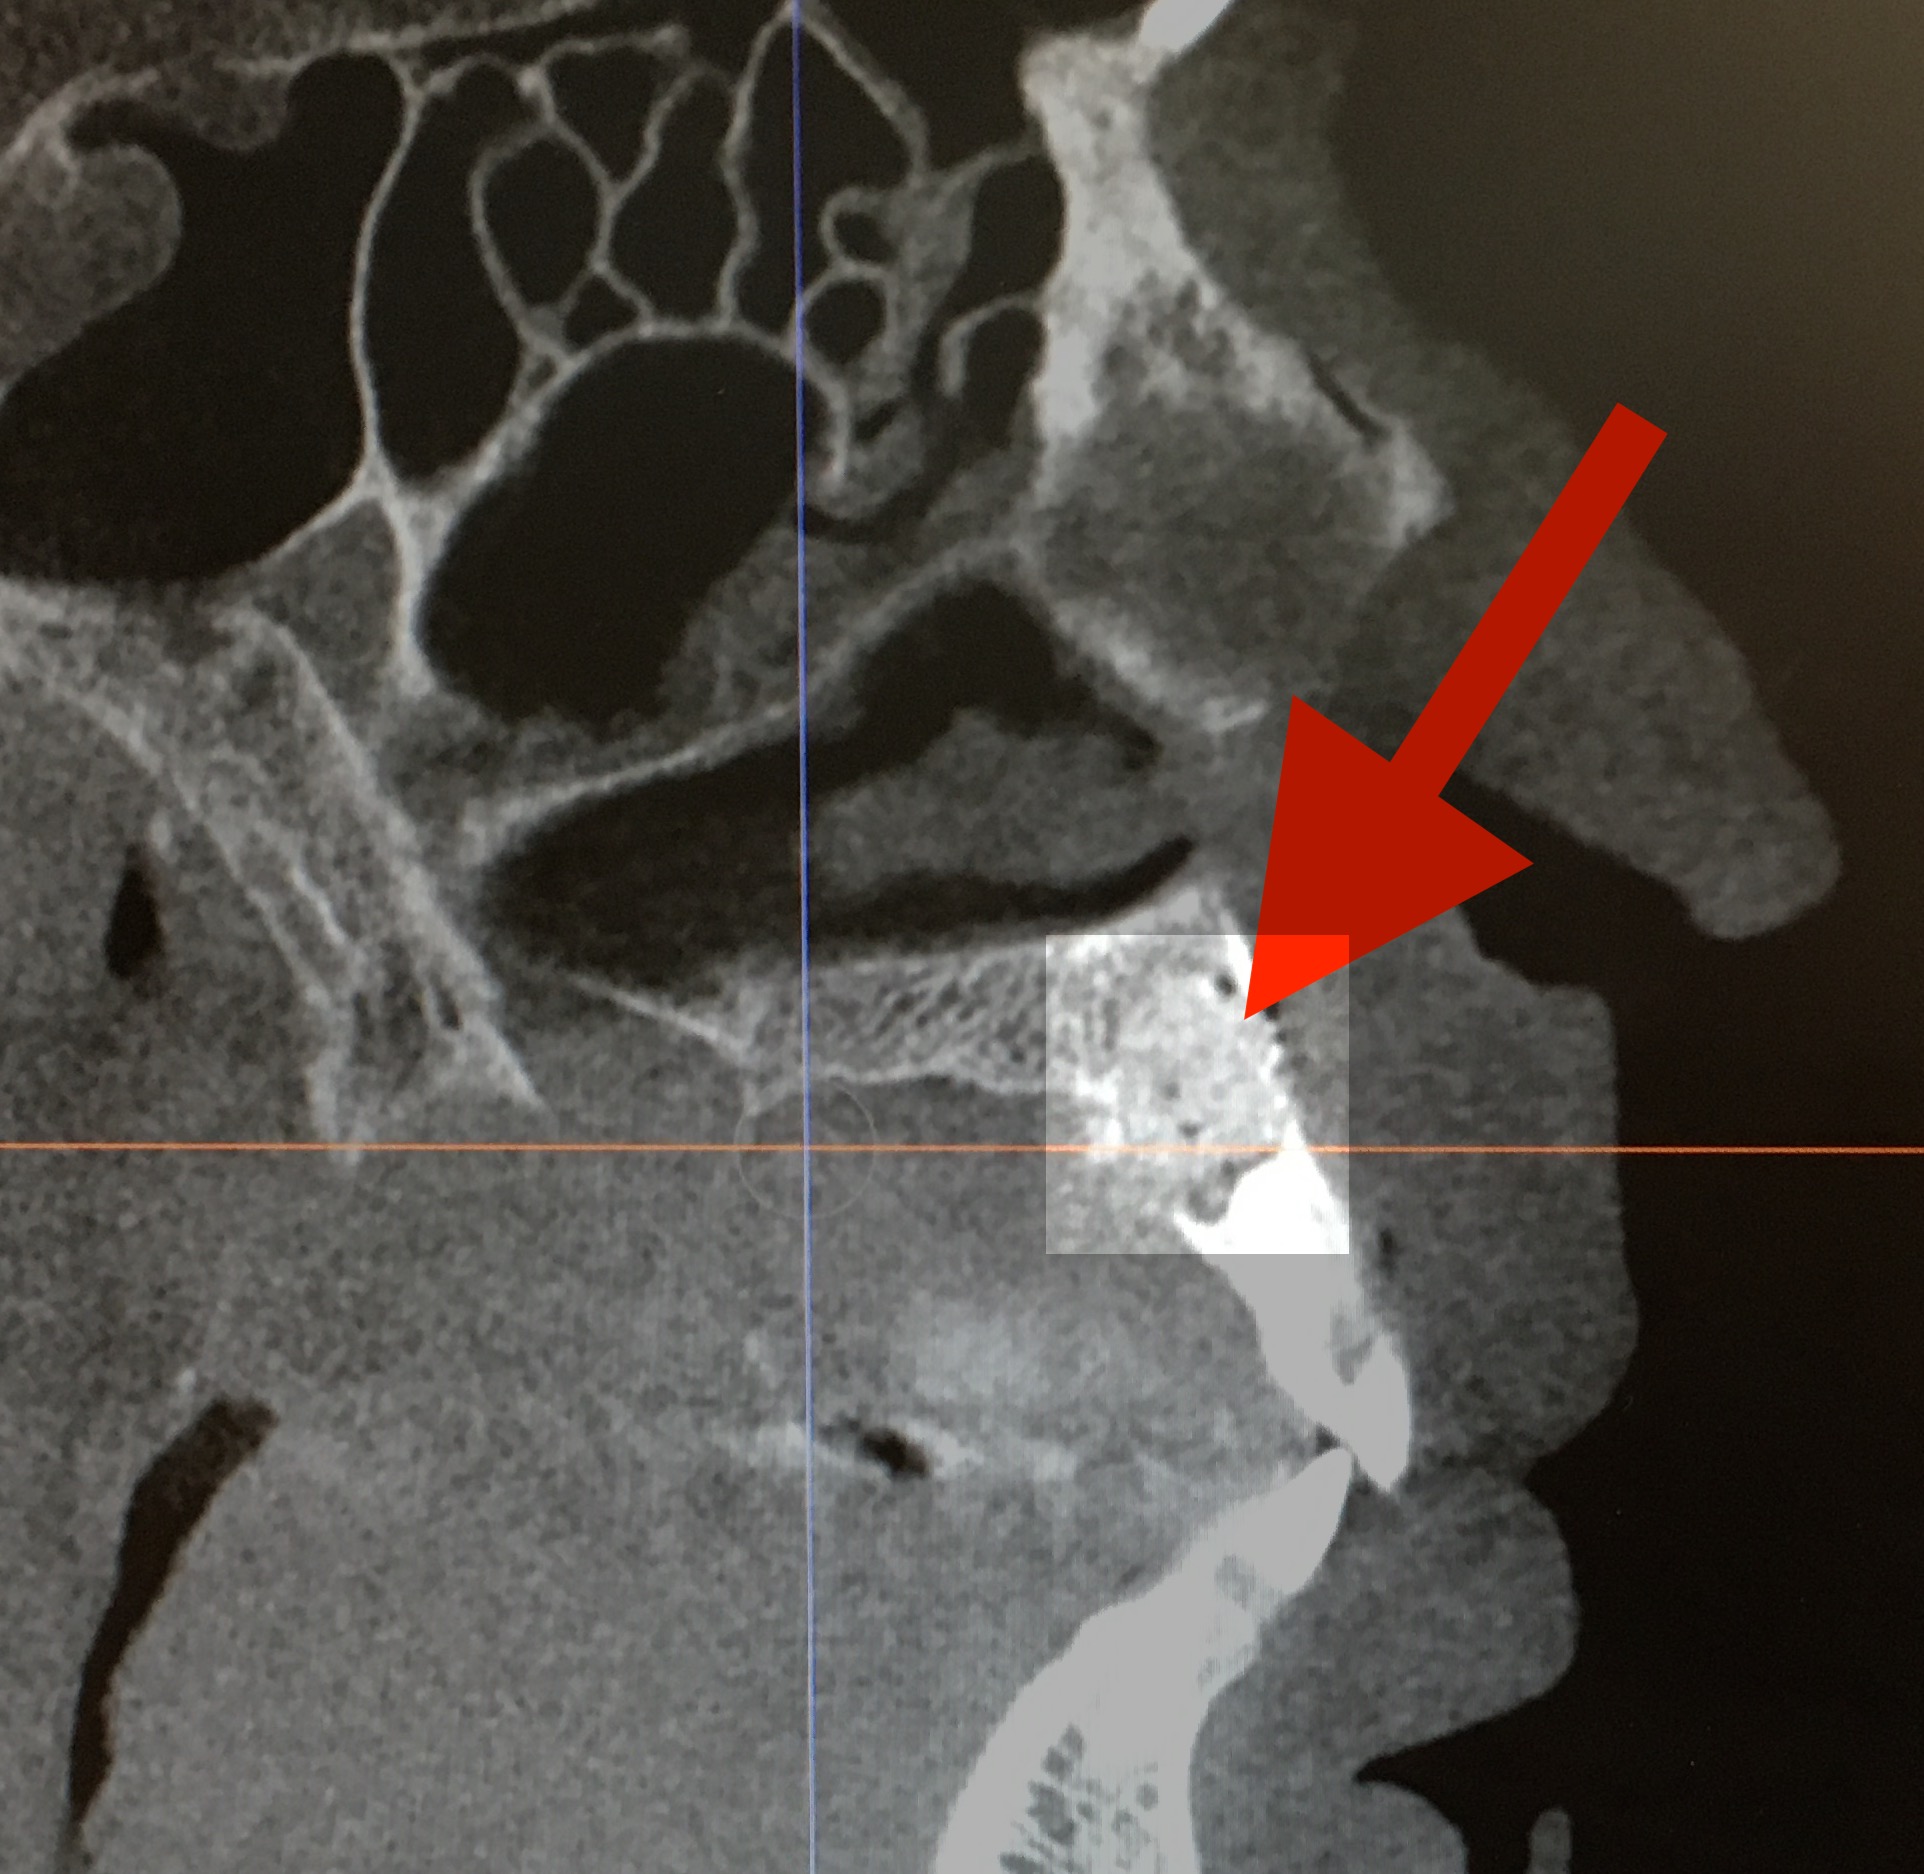

I was fascinated by this, imagining her filling the hole with a sand-like material, maybe using a funnel, like I do to fill the pepper mill. She showed me an X-ray she took after the surgery was completed and while I was still unconscious.

“There, that round spot is where I put the granulated bone. You can kind of see how it looks a little different than the area around it.”